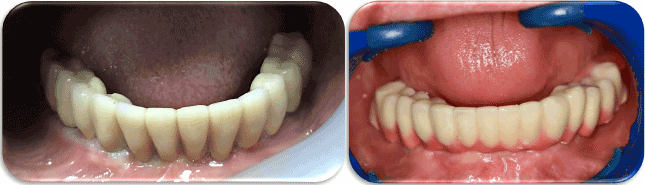

Figure 20. Final Splinted & Non-splinted prostheses Intra-Orally.

Figure 19. Final prosthesis on the cast.